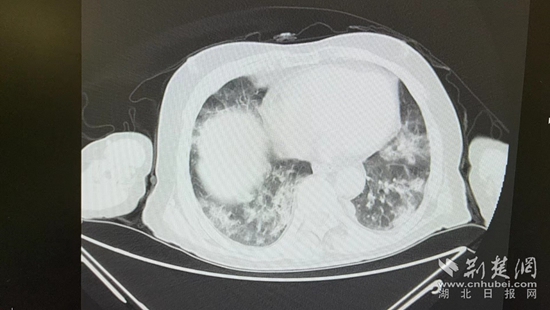

病情的突然惡化,會不會與近期的新冠病毒感染有關?雖然家屬反映,曾多次在家自測抗原正常,但徐濤還是力排眾議,說服老人進行核酸檢測和肺部CT檢查。結果顯示核酸陽性,60%白肺,結合老人的表現(xiàn),這正是一例典型的老年人“沉默性肺炎”。

胸部CT片。通訊員 供圖